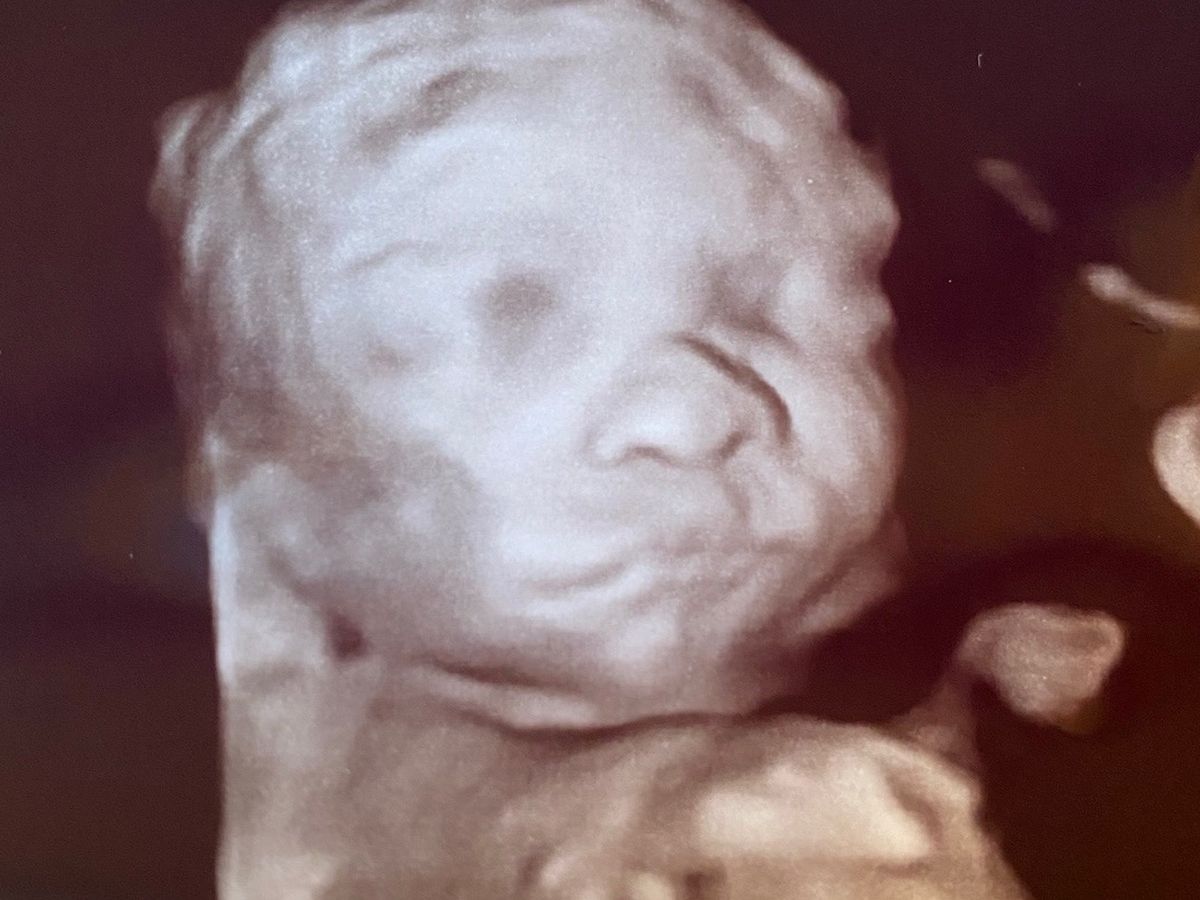

I am trying to raise money to help the Throne family for when they welcome baby Greyson into the world! He was diagnosed with T21 and has a double bubble! He will require surgery as soon as he is born! They have to deliver baby Greyson at VCU in Richmond va which is an 1hr 30mins away. He will be in the hospital for a month or long after birth! Brandy will be with him the whole time! And Joey is going to need to take off work to help with the other kids with school and trying to be up at the hospital to give brandy breaks. They are going to need help with gas, for him to get back and forth food for them while at the hospital and hotel stays! With Joey needing to be off work they will not have any money coming in. So I’m just trying to help them bring a little money in to help so that they are not stressing and can be there for their son while he heals. I realize that things are very tight with the whole COVID going on and holidays coming up but anything helps even if it’s just a share! Thank you to everyone! And just pray that Greyson is safe and heals quickly after surgery so that he can meet his wonderful family that can not meet him till he gets out the hospital!